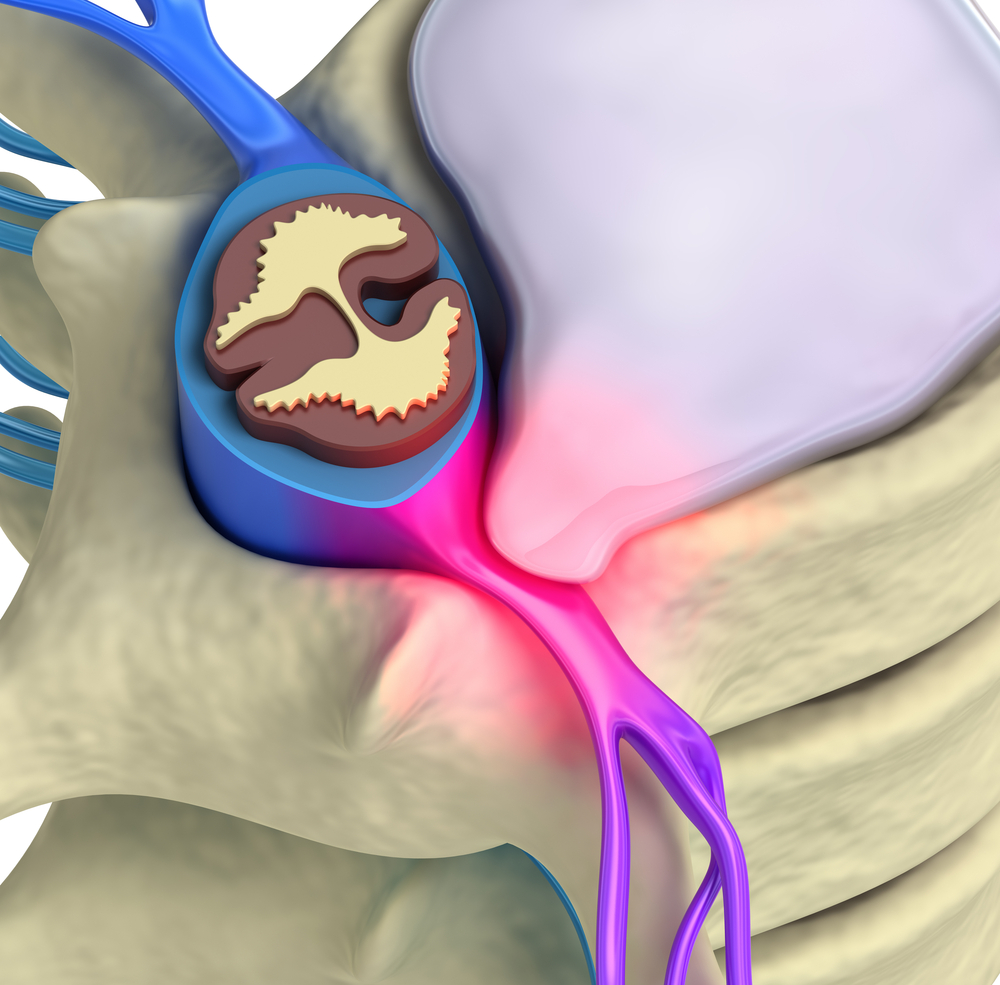

De mi is az a porckorong? Ez a gerinccsigolyák között található porcos réteg, mely gondoskodik arról, hogy gerincoszlopod a felegyenesedett életmód jelentette vertikális terhelésnek is rugalmasan tudjon ellenállni és a gerinccsigolyák ne koptassák egymást. Anyaga legjobban egy sűrű rosthálóhoz hasonlít, mely az említett rugalmasság mellett hatékonyan meg is támasztja a gerinc elemeit, amikor azok - a legtöbb emlős csigolyáival szemben - nem egymás mellett, hanem egymás felett, egymásra nehezedve helyezkednek el.

A porckorong szerkezete kettős: míg kívül erős rost alkotja, belül kocsonyás anyag. Utóbbi víztartalma a test öregedésével csökken, így változik annak rugalmassága is. E folyamat a csigolyák és csigolyaközök meszesedésével együtt oda vezethet, hogy a külső rostos szekció könnyebben szakadhat, a szakadás helyén pedig a belső rész előboltosul. Ezt nevezi a szakirodalom sérvnek. Ritka esetekben még ezen a ponton is fel tud lépni gyógyulás magától, általában azonban valamilyen orvosi beavatkozást igényel.

Társadalmunk nagy részét érinti az irodai munka jelentette kockázatcsomag, így az aszimmetrikus csigolyaterhelés is. Ez idővel az esetek többségében oda vezet, hogy a külső rostos rész valahol megsérül, és a belső zselés mag kiboltosul. A sérv ezzel létre is jött.

A sérvnek több fokozata is ismeretes: a legenyhébben a boltosulás csak apró, ritkábban magától vissza is húzódik megfelelő orvosi segítség és/vagy aktív ülést garantáló SpinaliS szék segítségével. Súlyosabb esetben azonban a külső rész teljesen átszakad és a belső kocsonyás szekció teljesen eltűnhet. Ez az igen erős fájdalom mellett a környező izomzatot arra ösztönzi, hogy a gerinc megbomlott egyensúlyát megpróbálja helyrehozni, ezt a csatát azonban nem lehet megnyerni. A mély hátizomzatban a plusz teher miatt idővel görcsös csomók alakulhatnak ki, amik csak fokozzák a fájdalmat és együttesen tovább csökkentik a mozgásképességet. Minél kiterjedtebb a probléma, annál több más területet érinthet: végső esetben már fellép a nyaki gerincszakasz elváltozása is, karöltve ízületi meszesedéssel és leépüléssel.